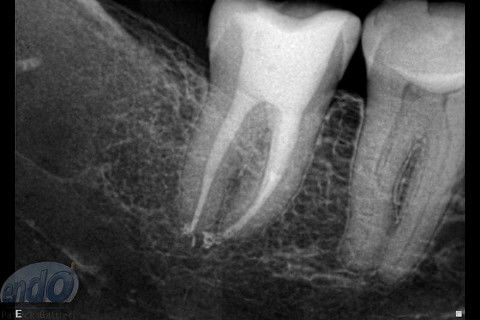

Tratamento Endodôntico dos Dentes 45 - 46 - 47

Seguem 3 casos clínicos realizados esta semana em uma cliente que está passando por um tratamento estético. O dente 47 apresentava calcificação da entradas dos canais radiculares, provavelmente, devido a uma pulpotomia realizada no passado. Desta forma, foi dedicada uma consulta de aproximadamente 2 horas para a realização deste procedimento. Os dente 45 e 46, por apresentarem canais radiculares com menor complexidade, foram tratados, simultaneamente, em sessão única com duração de aproximadamente 2 horas e 15 minutos.

Os três dentes foram tratados seguindo a técnica da FOP-UNICAMP, na qual é realizada patência e ampliação do forame apical. A instrumentação foi realizada com instrumentos rotatórios e como substância química auxiliar foram utilizados o ENDOGEL e o EDTA 17%. A irrigação ativa foi realizada com soro fisiológico. Os canais foram obturados com guta-percha e cimento PulpCanal Sealer, pela técnica de ondas contínuas de condensação.

Os procedimentos pré-restauradores nos dentes 46 e 47 envolveram apenas a confecção de núcleo de preenchimento em resina composta (Z250 B0,5). No dente 45 foi instalado um pino de fibra de vidro (FGM) e confeccionado núcleo de preenchimento em resina composta (Z250 B0,5).

O prognóstico é favorável e a longevidade destes dentes depende dos procedimentos restauradores que serão realizados na sequência do tratamento.